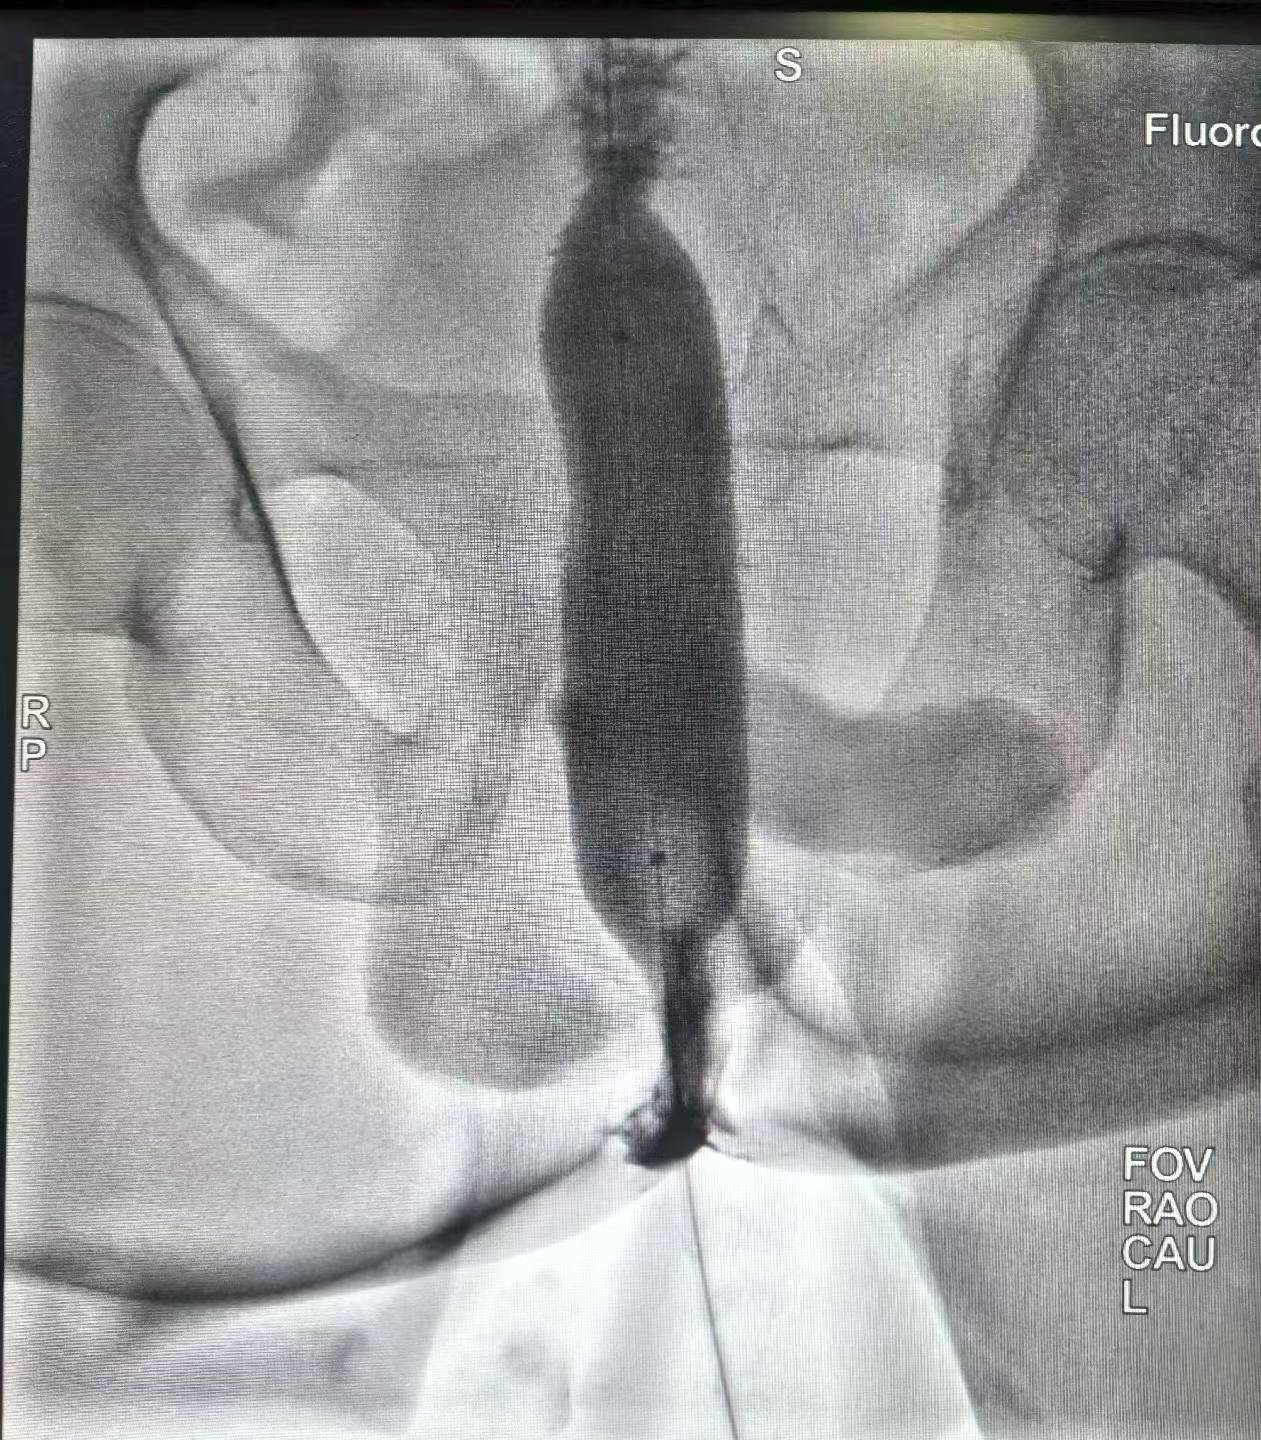

直肠癌术后吻合口狭窄(难治型)球囊扩张术。上午一台直肠癌术后吻合口狭窄经肛行球囊扩张术,球囊充分扩张后狭窄解除。介入球囊扩张对良性难治性狭窄,安全有效,术后即可排便顺畅。